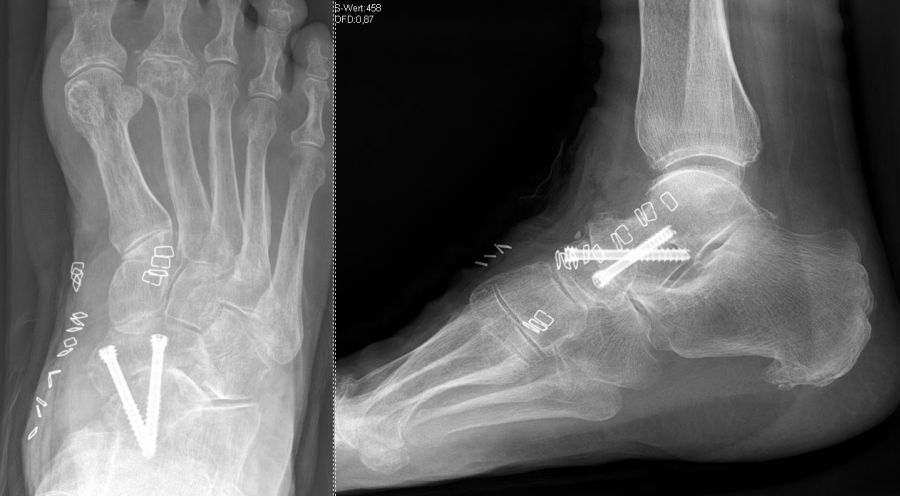

Degenerative Veränderungen zeigen sich am häufigsten im Bereich der Tarsometatarsalgelenke I-III-Gelenke 21. Hier kommt typischerweise eine Stabilisierung der medialen Säule mittels  Lapidusarthrodese und Arthrodese der Tarsometatarsalgelenke II und III in Frage. In seltenen, meist posttraumatischen Fällen ist auch die laterale Säule mit den Tarsometatarsalgelenken IV und V betroffen. Letztlich gilt es präoperativ zu erörtern, welche der Gelenke Lisfranc Gelenkreihe schmerzhaft sind, um diese gezielt versteifen zu können.

Es kommen verschiedene technische Möglichkeiten der operativen Versorgung in Frage.  Verwendung finden vor allem winkelstabile Plattensysteme, Schraubenosteosynthesen, Klammern, intraossäre Nagelsysteme, temporäre Kirschnerdraht-Transfixationen, Einbolzen von trikortikalem Span und Anlagerung von Spongiosa aus dem Beckenkamm oder dem Tibiakopf  (Abb. 2 und 3).

Durch die Arthrodese soll, wie oben beschrieben, eine Schmerzreduktion, eine Wiederherstellung der Fußstabilität und eine Korrektur der Fußstellung erreicht werden. Hierbei gibt es unterschiedliche Ansätze. Einige Autoren versteifen stets die mediale und laterale Säule bei TMT-Arthrosen 22. Andere Autoren sind der Meinung, dass nur die mediale Säule versteift werden sollte 18. Andere wiederum dehnen den Eingriff aus und beziehen die Cuneiforme-Gelenke mit in die Lisfranc-Arthrodese ein 21. Grundsätzlich zeigt sich der Trend, dass nur isoliert die arthrotischen und symptomatischen Gelenke versteift werden, ferner die Zugangswege klein und die Resektionsflächen der einzelnen Gelenke nur bis zur subchondralen Spongiosa eröffnet werden 23.